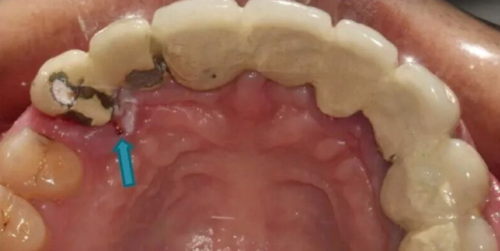

3、但是当患牙牙冠合龈高度过低,与对合牙咬合距离过低,无法用全冠甚至桩核冠形成良好的修复体固位。这时只能利用髓腔形成冠内固位形做位辅助固位或者主要固位,进行嵌体冠修复,因此髓腔固位冠应运而生(冠内固位形)。

髓腔固位冠(Endocrown)是以利用根管治疗后的牙体髓腔来固位并修复的一种新型冠修复体,即呈一圈对接式的边缘和位于髓腔内的核固位体。

(2)患牙临床牙冠过短,颌间距离不足,根管细小或弯曲、根管钙化等不适合桩核冠固位,可采用髓腔固位冠修复。

(3)患牙牙体大面积缺损,但为了提供足够的固位力,剩余牙体组织边缘应位于龈上,存留轴壁的高度和厚度均应不小于1mm。

(4)患牙髓腔形态正常且有一定深度(≥2 mm)